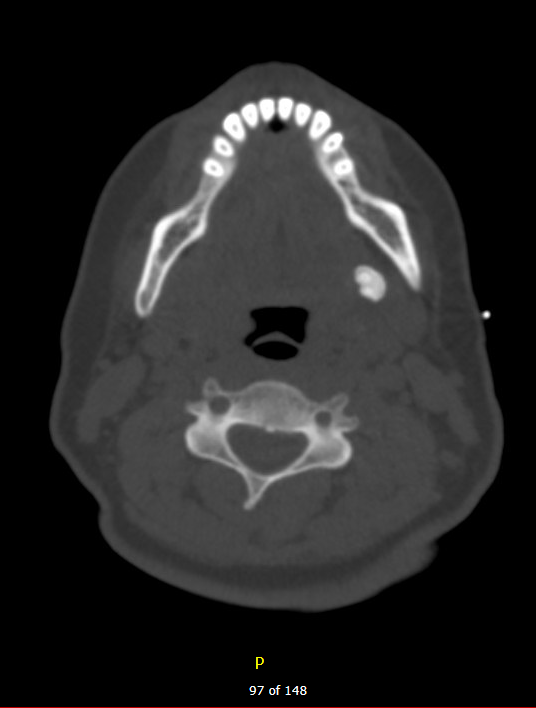

Diagnostic testing. A computed tomography (CT) scan without contrast was performed shortly after initial presentation to further investigate the cause of her chronic pain and swelling (Figures 1 and 2). The CT revealed a calculus in the dorsal aspect of the left submandibular duct that measured approximately 1.1 x 0.8 x 1.1 cm in anteroposterior, transverse, and coracoclavicular dimensions, respectively. The nasopharynx and oropharynx were within normal limits. Soft tissue planes of the adjacent parapharyngeal spaces were maintained. No distinct radiopaque calculus was noted otherwise along the course of Wharton or Stensen ducts, nor was there evidence of distention of the proximal aspect of Wharton duct on the left despite the described calculus. The submandibular and parotid glands otherwise appear to be within normal limits. Specifically, there was no evidence of acute sialadenitis. The hypopharyngeal, supraglottic, glottic, and subglottic airways were within normal limits. The soft tissue planes of the upper neck were otherwise maintained. No significant lymphadenopathy was seen by size criteria. Based on these results, it was confirmed that the patient had a sialolith of the left submandibular gland.

Figure 1. A bone mode/hard tissue condition coronal head plain CT imaging of a 12 mm submandibular sialolith.